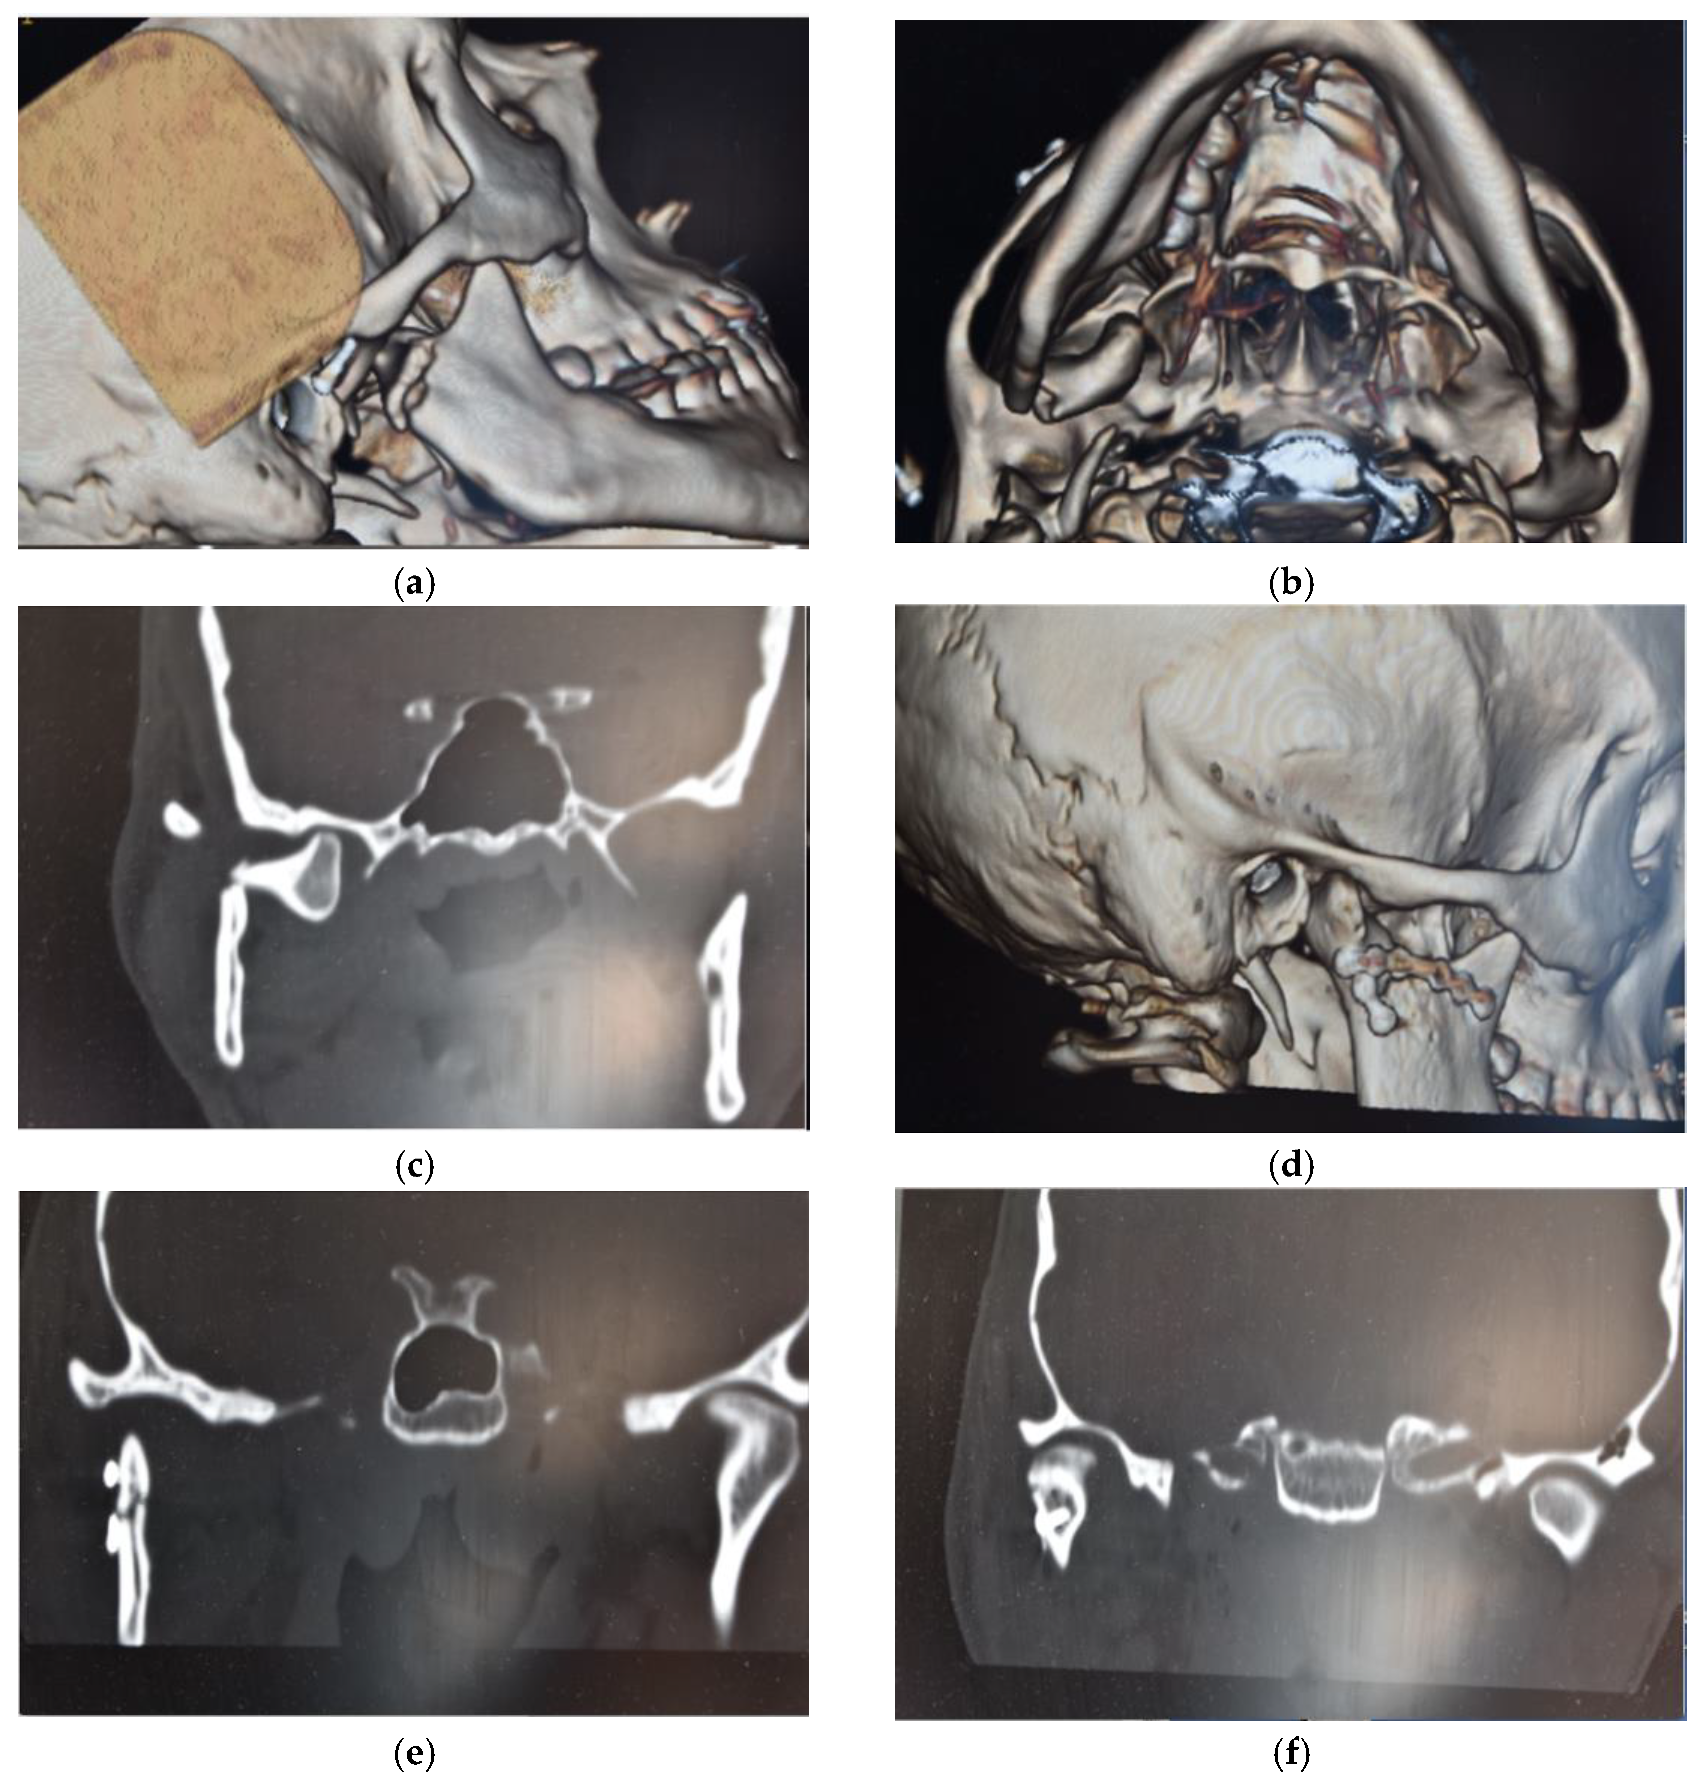

Surgical treatment was performed in patients with widely displaced fractures with lack of contact between the two fragments (Figure 1, Figure 2, Figure 3 and Figure 4), or when the displacement of the fragments caused a lack of function of the TMJ that could not be resolved with conservative treatments, or in multiple fractures of the middle third of the face in order to use the mandible as a guide for replacement of the bones of the middle third of the face, as previously described [8].

Figure 4. (a,b) Pre-operatory volumetric CT; (c) pre-operatory coronal CT; (d) post-operatory volumetric CT; and (e,f) post-operatory coronal CT of patient #4.